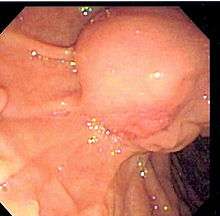

The diagnosis of choledocholithiasis is suggested when the liver function blood test shows an elevation in bilirubin and serum transaminases. Other indicators include raised indicators of ampulla of vater (pancreatic duct obstruction) such as lipases and amylases. In prolonged cases the INR may change due to a decrease in vitamin K absorption. (It is the decreased bile flow which reduces fat breakdown and therefore absorption of fat soluble vitamins). The diagnosis is confirmed with either an MRCP (magnetic resonance cholangiopancreatography), an ERCP, or an intraoperative cholangiogram. If the patient must have the gallbladder removed for gallstones, the surgeon may choose to proceed with the surgery, and obtain a cholangiogram during the surgery. If the cholangiogram shows a stone in the bile duct, the surgeon may attempt to treat the problem by flushing the stone into the intestine or retrieve the stone back through the cystic duct.

On a different pathway, the physician may choose to proceed with ERCP before surgery. The benefit of ERCP is that it can be utilized not just to diagnose, but also to treat the problem. During ERCP the endoscopist may surgically widen the opening into the bile duct and remove the stone through that opening. ERCP, however, is an invasive procedure and has its own potential complications. Thus, if the suspicion is low, the physician may choose to confirm the diagnosis with MRCP, a non-invasive imaging technique, before proceeding with ERCP or surgery.